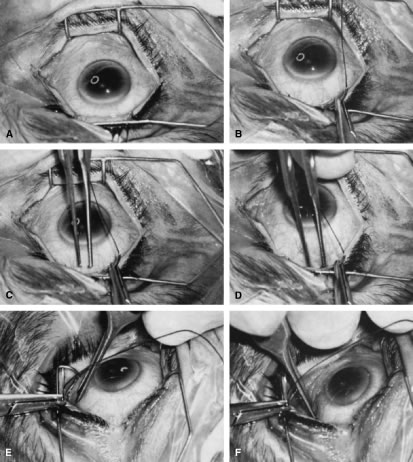

Back to Top